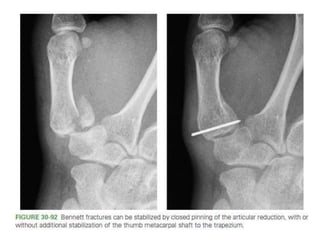

Carpometacarpal (CMC) Fractures •The normal ROM at the thumb CMC joint • 50 degrees of flexion-extension • 40 degrees of abduction-adduction • 15 degrees of pronation-supination.